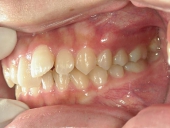

矯正歯科 治療前 右

矯正歯科 治療前 左